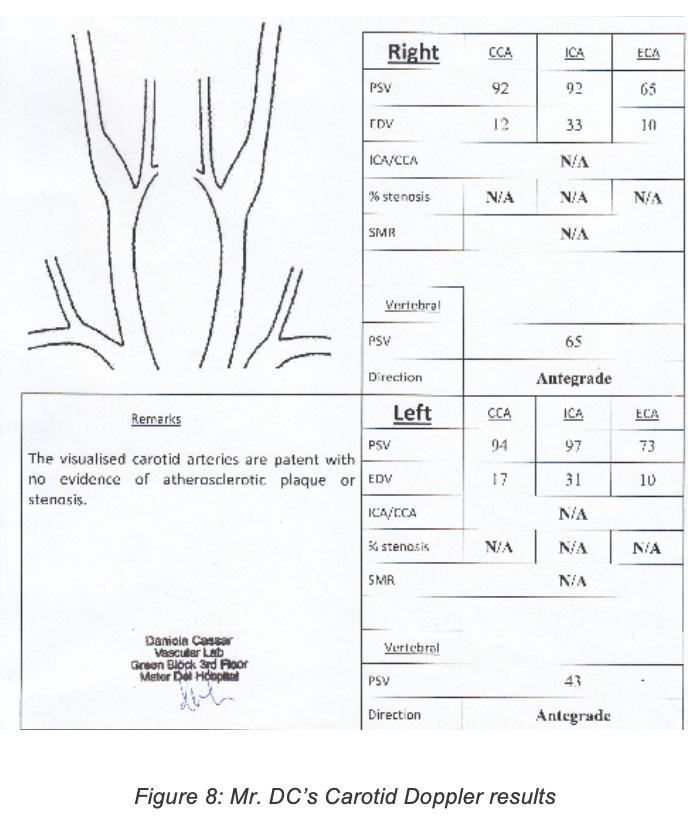

Investigations ordered: 1. ECG – To identify any predisposing conditions which may have resulted in the stroke e.g.: Atrial fibrillation/flutter, acute myocardial infarction, infective endocarditis etc. In case any are identified, further prophylactic treatment may be indicated. 2. Routine bloods (Complete Blood Count, ESR, CRP, Urea and Electrolytes, Blood Glucose Levels etc) – to rule out underlying conditions such as sepsis, renal disease and diabetes. Inflammatory markers are often raised in ischaemic stroke. In case any are identified, further treatment may be indicated. 3. CT brain – To determine whether the stroke was ischaemic or haemorrhagic in nature, to properly locate the lesion and to rule out any possible differentials such as space occupying lesions. 4. Echocardiogram – To rule out any underlying structural heart disease which may have caused the stroke e.g.: Valvular heart disease, patent foramen ovale, atrial septal aneurysm etc. In case any are identified further prophylactic treatment may be indicated. 5. Carotid doppler ultrasound – To identify any possible stenosis or plaque build-up in the carotid arteries which may predispose to recurrent strokes. If stenosis is greater than 50%, carotid endarterectomy may be indicated. 6. Geriatric review 7. Stroke rehabilitation including outreach to physiotherapy, occupational therapy and

Mr DC’s ECG revealed atrial flutter, a possible source of emboli which may have resulted in the stroke. C-Reactive Protein was found to be 51.9 mg/L (normal range <3.0 mg/L). This is common in stroke patients since acute ischaemic stroke may trigger an inflammatory response in the surrounding tissues. No abnormalities seen on the echocardiogram. Carotid doppler showed no stenosis or atherosclerosis of the carotid arteries. Carotid doppler results are shown below: